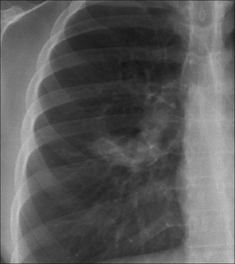

image Mucus plugging may cause a lobe to collapse.

image

Figure 29.2 Acute asthma. Unexplained clinical deterioration. Collapse of the left lower lobe due to a mucus plug in the bronchus.